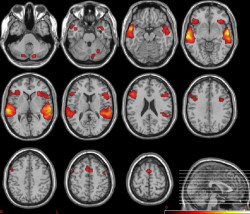

La contaminación del aire aumenta el riesgo de demencia de las mujeres

Las mujeres mayores que viven en lugares con niveles más altos de contaminación del aire pueden tener más encogimiento cerebral del tipo que se observa en la enfermedad de Alzheimer, frente a las mujeres que viven en lugares con niveles más bajos, según un nuevo estudio publicado en línea en `Neurology`, la revista médica de la Academia Estadounidense de Neurología.

Las neuronas despojadas de su identidad son el sello distintivo de la enfermedad de Alzheimer

Investigadores de la Universidad de California en San Diego han identificado nuevos mecanismos en las neuronas que causan la enfermedad de Alzheimer. Concretamente han descubierto que los cambios en la estructura de la cromatina, la forma muy enrollada del ADN, provocan que las neuronas pierdan su función especializada y vuelvan a un estado celular anterior. Esto da como resultado la pérdida de conexiones sinápticas, un efecto asociado con la pérdida de memoria y la demencia.